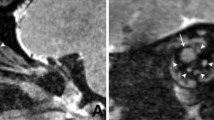

Figure 3 shows the temporal signal changes in the 3D-T2W sequences. Similar to the T2 value changes, the SIR of samples administered with Gd and 17O showed remarkable changes, whereas no remarkable temporal changes were observed in the other solutions. Figure 4 shows a comparison of the sequences of SIR in 3D-T2W and HASTE for Gd and 17O, with the data obtained for 3D-T2W being the same as that shown in Fig. 3. Longer TEs showed more remarkable changes, indicating that both sequences can be highly sensitive to signal changes by applying a super-long TE.

Temporal changes in signal intensity ratio (SIR) using 3D T2-weighted sequences in the anterior chamber and vitreous cavity with the administration of each topical eye drop solution. Echo time (TE) of 500 ms (a, b), 3200 ms (c, d), and 4500 ms (e, f). The SIRs with gadobutrol and H217O showed temporal changes, whereas the others showed no obvious changes. The application of longer TEs resulted in a remarkable SIR change

Sequence comparison of signal intensity ratio (SIR) in the anterior chamber and vitreous cavity with the administration of gadobutrol (Gd) and H217O (17O). The sequence is as follows: 3D T2-weighted with echo time (TE) of 500, 3200, and 4500 ms, HASTE with TE of 440 and 3000 ms. The SIRs for TE500 and HASTE440 showed similar changes; even the HASTE sequence provided great signal changes by applying a super-long TE

Figure 5 shows representative images (presented only for the samples treated with Gd and 17O). After Gd administration, the TE500 image showed a visual signal decrease in the anterior chamber at 4 h and a strong signal decrease in the vitreous cavity at 26 h; the TE3200 image showed a visual signal decrease in the anterior chamber at 1 h and a decrease in the vitreous peripheral signal at 8 h. After 17O administration, the signal decrease in the anterior chamber was observed on the graph for TE500 (Fig. 3a), but it was visually obscure, and there might be a slight signal decrease visually in the vitreous cavity after 12 h. The TE3200 image showed a visual signal decrease in the anterior chamber at 0.5 h, and a gradual signal decrease in the vitreous cavity from the periphery at 1 h. In both solutions with TE4500, the tendency for signal decrease was more remarkable compared to TE3200. In 3D-real IR images, only the Gd sample showed a strong signal increase. Signal increases in the anterior chamber were observed at 0.5 h, and their distribution in the vitreous cavity gradually increased at 2 h and later.